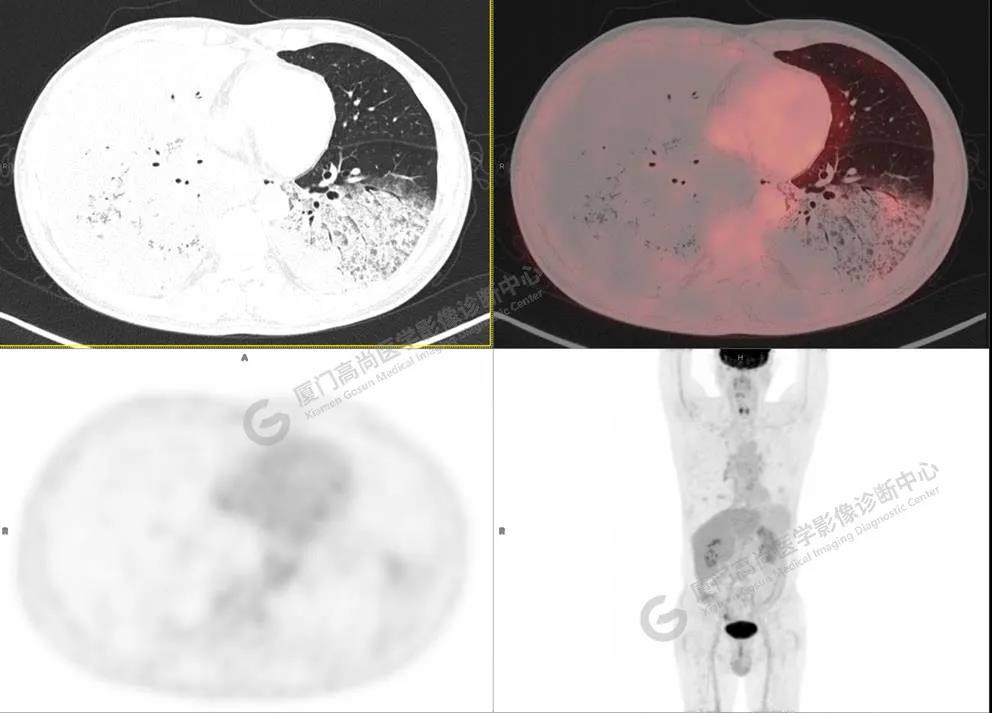

PET/CT影像圖

圖1

PET/CT所見(jiàn):雙肺大片實(shí)變影及磨玻璃影,部分呈地圖樣改變,累及右肺尖,部分放射性攝取輕微增高,SUVmax 1.77,其內(nèi)見(jiàn)多發(fā)支氣管充氣征象。

影像診斷: 雙肺大片實(shí)變影及磨玻璃影,大部分代謝不高,局部代謝輕微增高,考慮肺泡蛋白沉積癥,建議病理學(xué)檢查或肺泡灌洗物檢查。